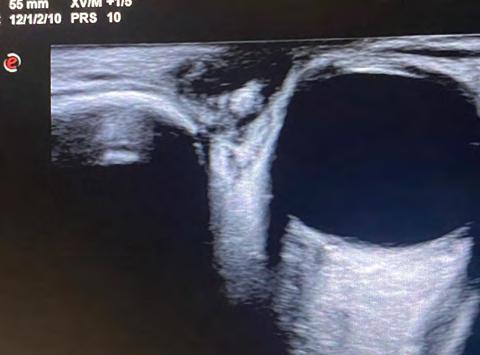

Se realiza ecografía ocular (opcional) en ambos pacientes para confirmar la sospecha.

Por su manifestación inicial, la miasis ocular puede confundirse con orzuelo, chalazión o celulitis preseptal. Es importante considerar que, si bien es poco frecuente en zonas apartadas del trópico, su diagnóstico debe tenerse en cuenta en personas que han viajado a lugares endémicos y dicha información debe relevarse en la anamnesis. Si luego de la exploración exhaustiva persiste la duda, puede indicarse una ecografía para dar un diagnóstico certero.